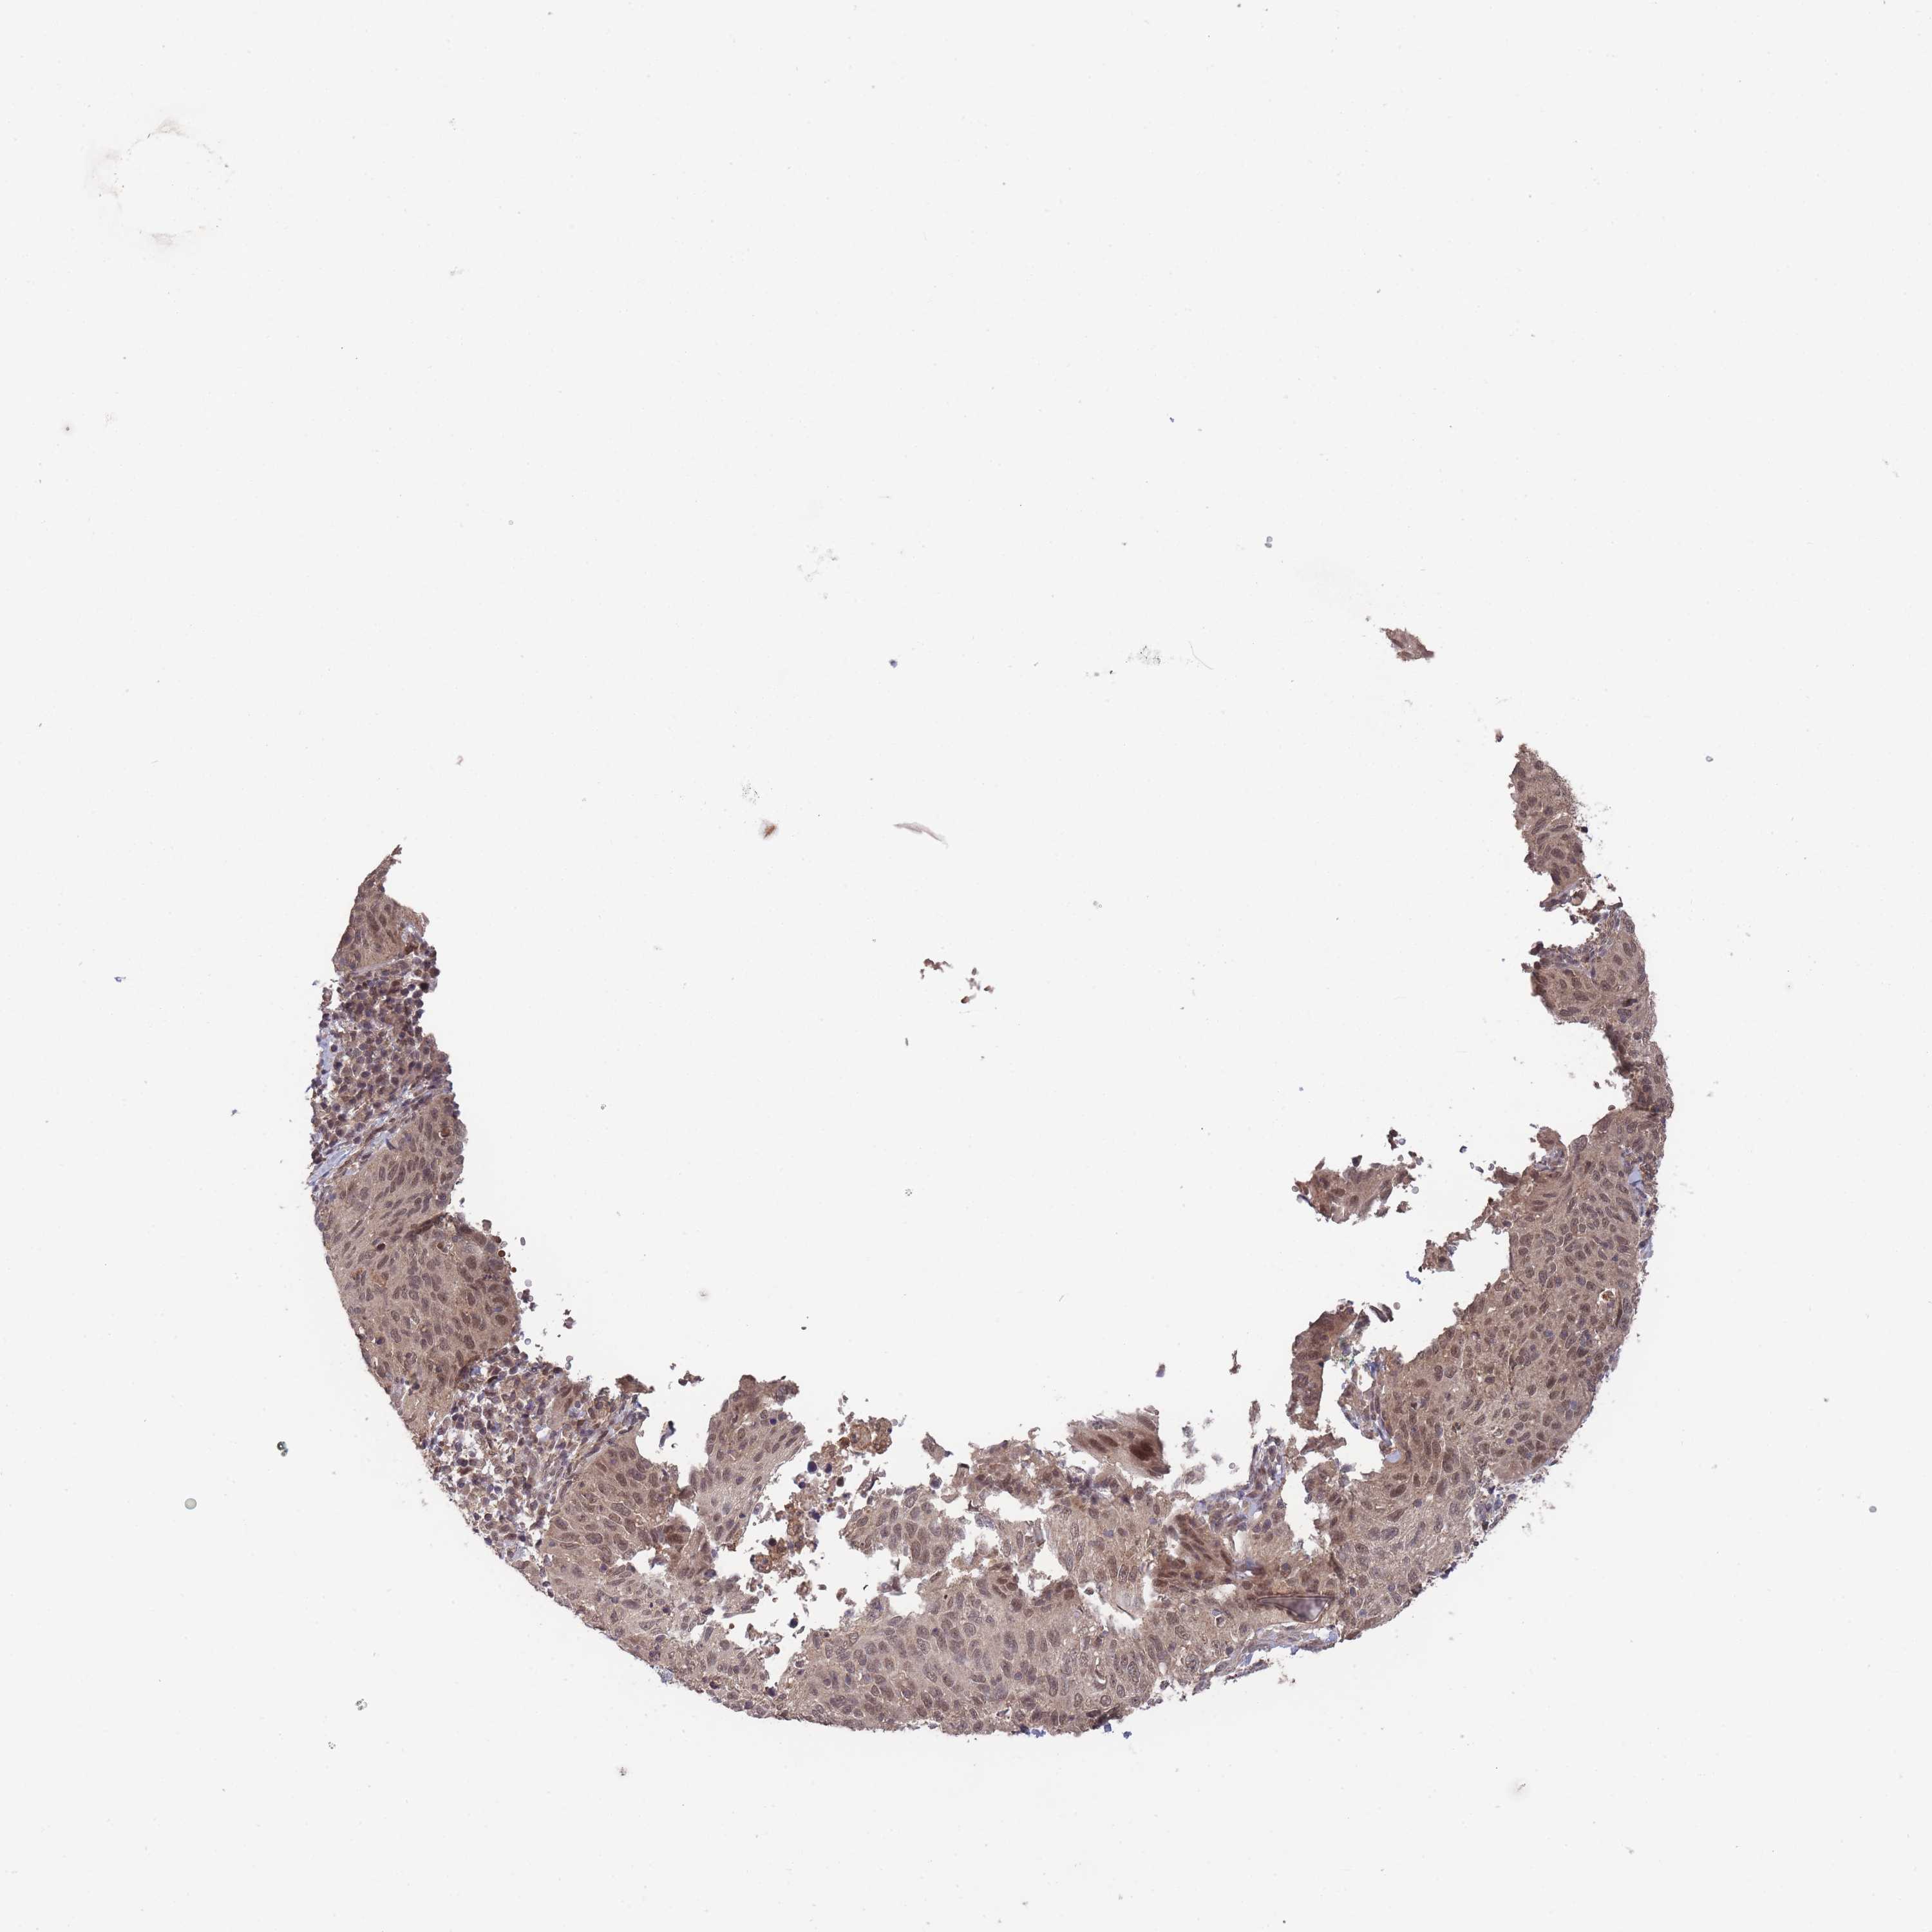

CERVICAL CANCER - Protein expressioni

A mouse-over function shows sample information and annotation data. Click on an image to view it in a full screen mode. Samples can be filtered based on level of antibody staining by selecting one or several of the following categories: high, medium, low and not detected. The assay and annotation is described here.

Note that samples used for immunohistochemistry by the Human Protein Atlas do not correspond to samples in the TCGA dataset.

Antibody stainingi

Antibody staining in the annotated cell types in the current human tissue is reported as not detected, low, medium, or high, based on conventional immunohistochemistry profiling in selected tissues. This score is based on the combination of the staining intensity and fraction of stained cells.

Each image is clickable and will lead to virtual microscopy that enables deeper exploration of all samples and also displays staining intensity scores, fraction scores and subcellular localization as well as patient and tissue information for each sample.

Antibody HPA050275

Staining

High

Medium

Low

Not detected

Intensity

Strong

Moderate

Weak

Negative

Quantity

>75%

75%-25%

<25%

None

Location

Nuclear

Cytoplasmic/membranous

Cytoplasmic/membranous,nuclear

Adenocarcinoma, NOS